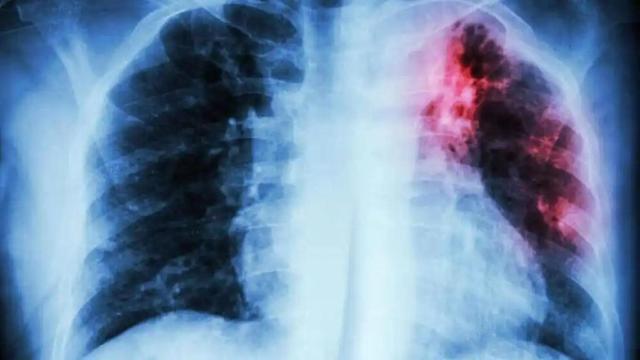

Oncología radioterápica